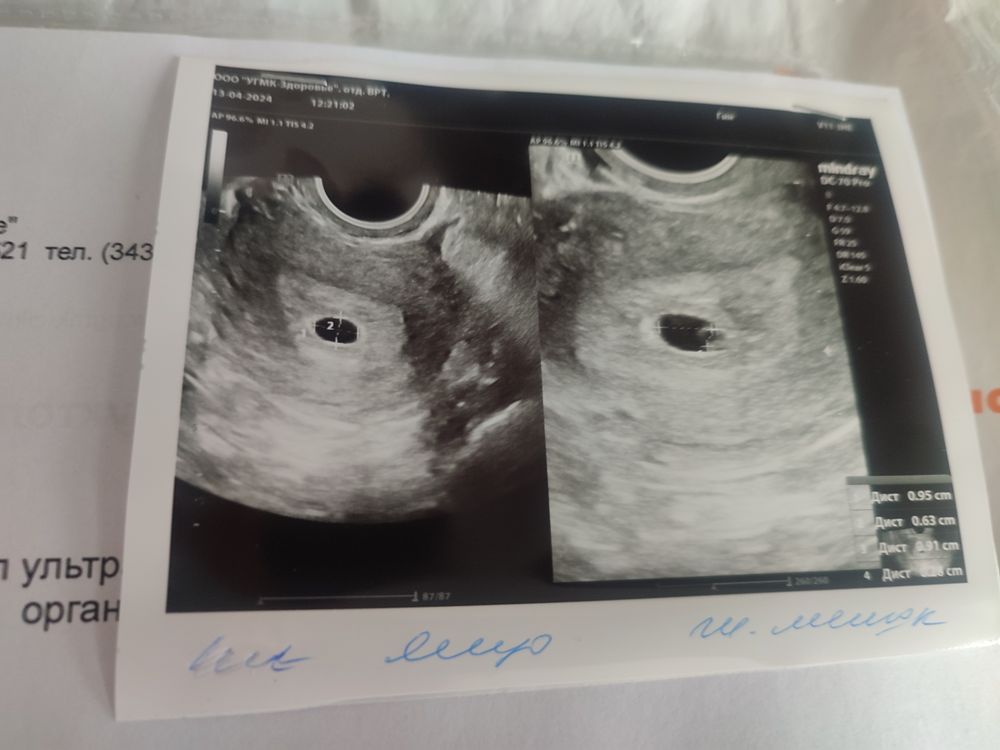

хорошая девочка, нет, только на 19 дпп светло розовые скудные выделения были ( сосудик лопнул как мне Ре объяснила), но мне пока что полностью запретили половой акт )) Изображение

хорошая девочка, увидели и плодное яйцо и желточный мешочек, через неделю на УЗИ сердечко слушать )